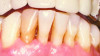

Bleeding: not a good predictor of disease activity. Bleeding on probing (BOP) represents an inflammatory infiltrate in the connective tissue, a reduction of collagen, and ulceration of the pocket's epithelial lining (Figure 2 and Figure 3).18 However, bleeding does not indicate the severity of periodontal lesions, and BOP is not a good predictor of disease activity.19 The term "disease activity" denotes there is ongoing clinical attachment and/or bone loss. Conversely, the absence of BOP is a good forecaster of clinical health and long-term tooth retention.19 Thus, BOP is an excellent indicator of the need for therapy, and its elimination is an important clinical endpoint.

Fig 3. Gingival biopsy from a site that did not bleed upon probing. Note there is no inflammatory infiltrate and the collagen (reddish area) is intact. (Fig 2 and Fig 3 are courtesy of Jack Caton, DDS.)

Figure 3